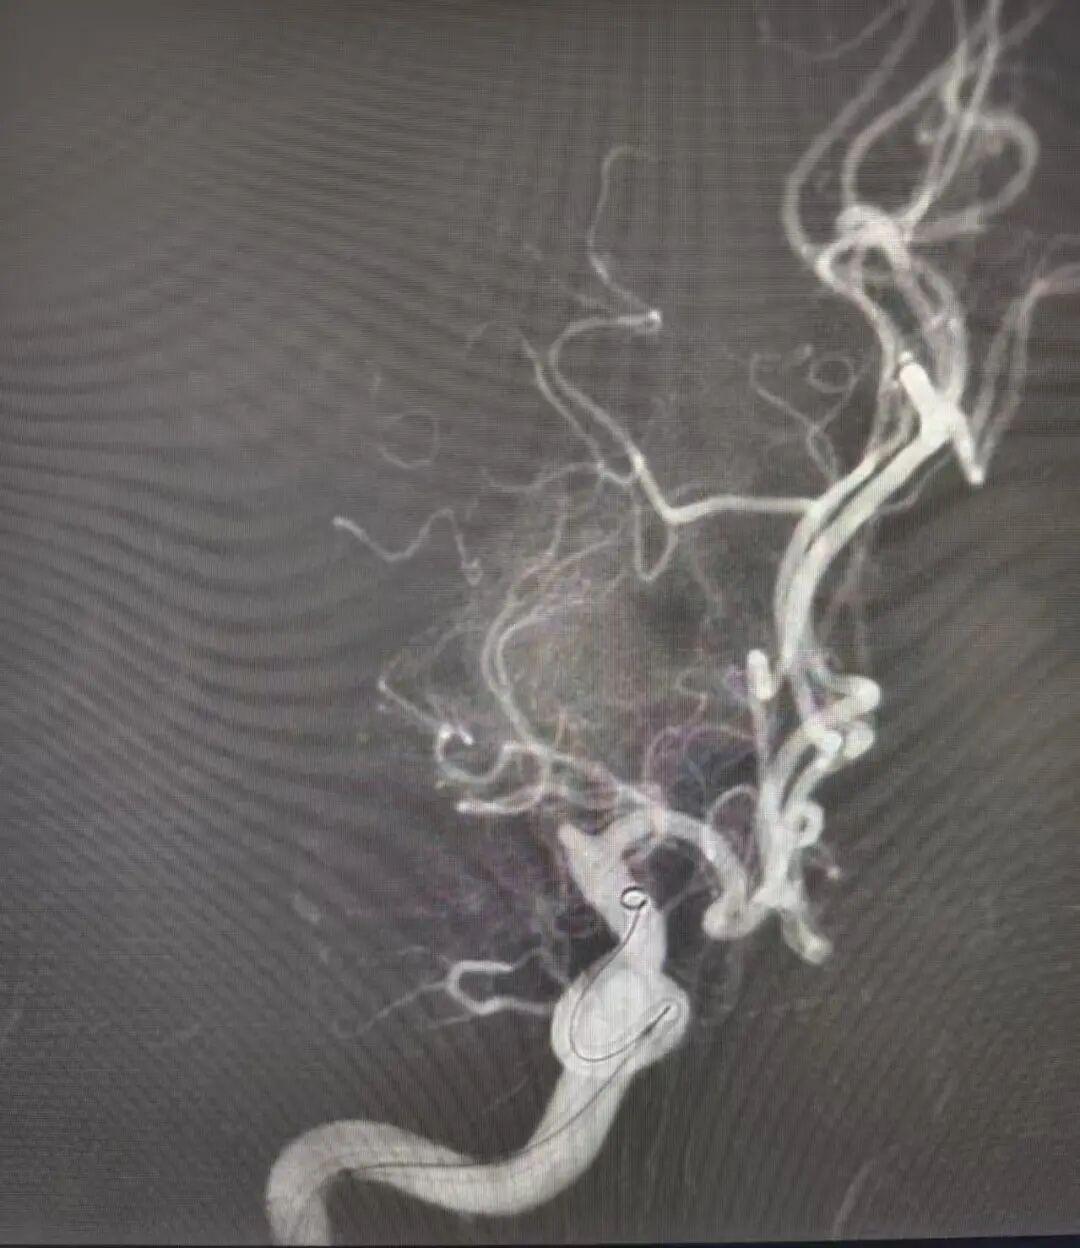

董冀晨副主任医师沉稳操作取栓支架,在焦文强主治医师的密切配合下,成功将堵塞血管的血栓完整取出。术后造影显示,原本闭塞的血管瞬间恢复通畅,血流重新奔涌。

术前

术后